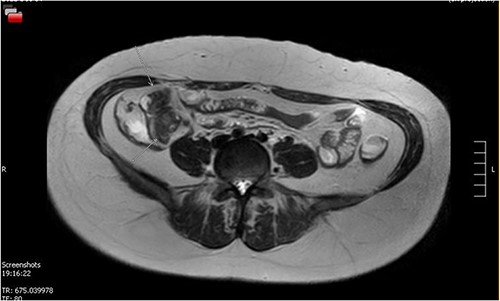

Her MRE showed a small bowel lesion ~10 cm proximal to the ileocaecal valve, favoured to represent a Meckel’s (Fig. 2). A colonoscopy was done to exclude a diagnosis of Crohn’s disease. A colonoscope was passed into the TI and advanced a further 5 cm, with normal mucosa throughout.

MRE showing small bowel lesion ~10 cm proximal to the ileocaecal valve.